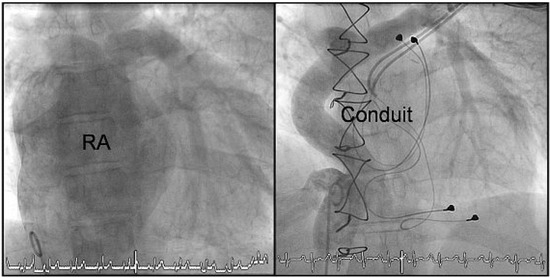

Die Fontan-Konversion—Oder das Schicksal, Die Erste zu Sein

We report the case of the first patient with tricuspid atresia in whom an “old-fashioned” Fontan operation with an atriopulmonary anastomosis was performed in our hospital 18 years ago. Complications of the former “classical” Fontan circulation can include progressive right atrial dilatation leading [...] Read more.

We report the case of the first patient with tricuspid atresia in whom an “old-fashioned” Fontan operation with an atriopulmonary anastomosis was performed in our hospital 18 years ago. Complications of the former “classical” Fontan circulation can include progressive right atrial dilatation leading to tachyarrhythmias, flow energy loss, obstruction of pulmonary veins, right atrial thrombi and the formation of pulmonary arteriovenous fistulas. In order to palliate our patient from recurrent atrial tachyarrhythmias and increasing haemodynamic disturbances, the previous “old-fashioned” Fontan circulation was surgically revised and converted according to a “modern” type of extracardiac Fontan circulation with additional anti-arrhythmic procedures. The post-operative course was uneventful. After recovery from surgery, the patient’s quality of life improved. She is free from atrial tachycardias and shows an increased exercise capacity. We will briefly discuss the complications of the classical Fontan circulation and the possible risks of the Fontan conversion. After having been the first Fontan patient in our center, our patient was again the first to require a major revision of its circulation. Full article